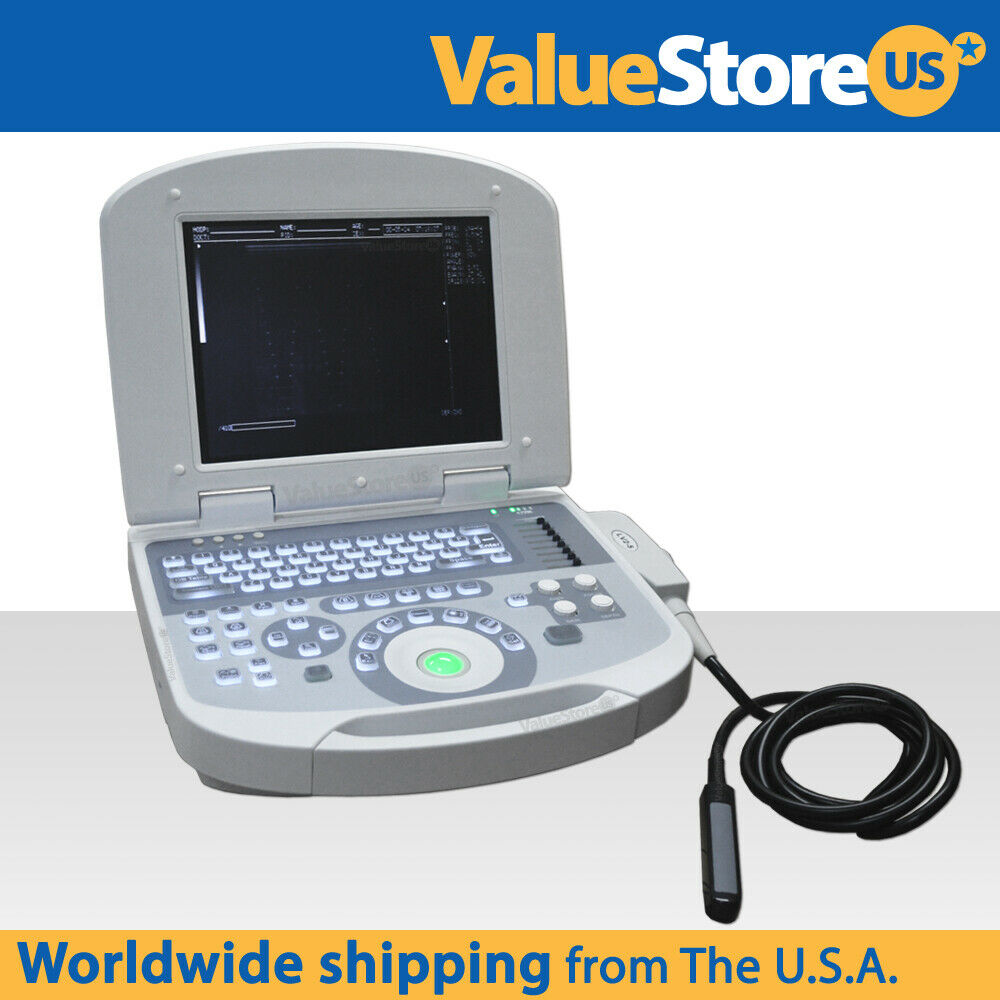

Ultrasound Scanner Laptop Machine Ultrasonic Machine Convex Rectal Transducer